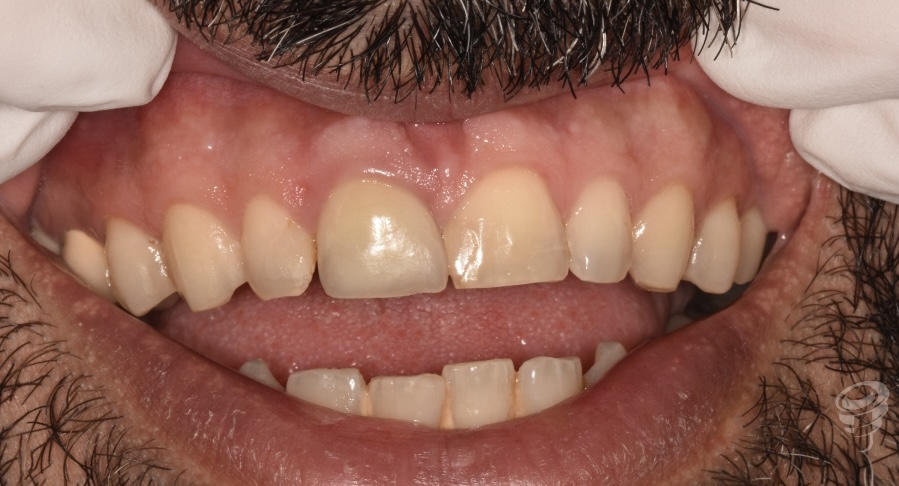

Caso Clínico | Rehabilitación Estética Integral con implante inmediato, injerto óseo y de tejido conectivo y carillas de cerámica en incisivo central superior fracturado

- Caso clínico: Paciente masculino de 45 años con fractura irreparable del incisivo central superior derecho (11) previamente tratado con una endodoncia y unión colado, fracturado por trauma oclusal. Se realizó extracción atraumática, colocación de implante inmediato, injerto óseo xenogénico mezclado con hueso antólogo del fresado, e injerto de tejido conectivo subepitelial para optimizar el perfil de emergencia. A los 4 meses se colocó corona implanto-soportada de zirconio y carillas de disilicato de litio en dientes 12 y 21.

La pérdida de un incisivo central superior por trauma representa un desafío estético y funcional de alta exigencia. Los implantes inmediatos, combinados con procedimientos de regeneración ósea y de tejidos blandos, permiten preservar la arquitectura alveolar y gingival, minimizando el tiempo de tratamiento y mejorando la predictibilidad estética (1).

Figura 3